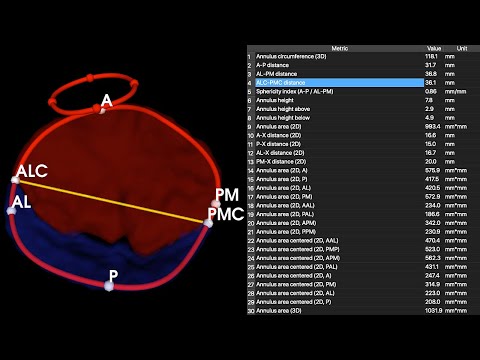

We are thrilled to publish our description of #SlicerHeart, a open source, cardiac-focused image processing extension for @3DSlicerApp that has now been downloaded over 44,000 times. frontiersin.org/articles/10.33…